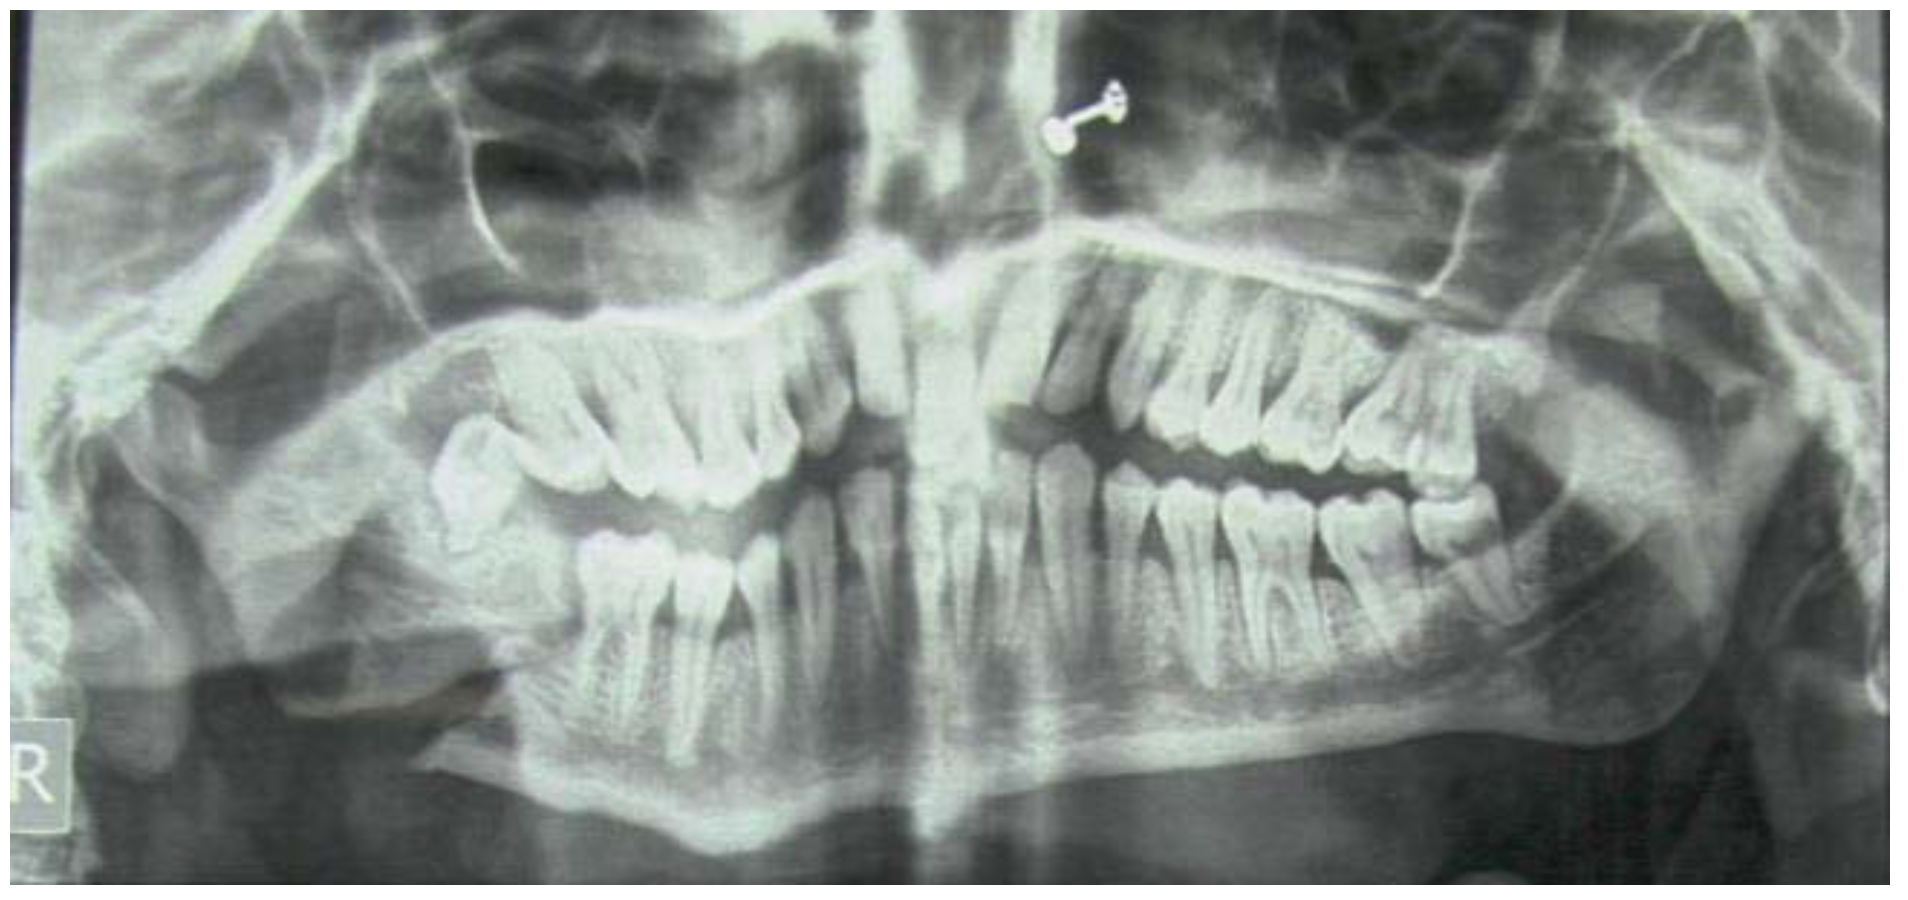

Orthopantomogram (OPG) revealed fracture of the right angle and left coronoid process. Oral hygiene was poor with severe halitosis.

Figure 1.

Initial presentation of the patient.

Figure 1.

Initial presentation of the patient.

During this period, pain had increased remarkably and the sleep was disturbed. Ingestion of liquids had become progressively difficult leading to dehydration. OPG revealed a fracture line each at right angle and left coronoid process of the mandible.

Figure 2.

Orthopantomogram (OPG) showing right angle and left coronoid fracture (Pre-op).

Figure 2.

Orthopantomogram (OPG) showing right angle and left coronoid fracture (Pre-op).